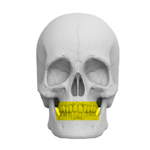

Zakres pracy tomografu.

(Badanie CBCT)

Szczęka ( 10 cm x 5 cm )

Żuchwa ( 10 cm x 5 cm )